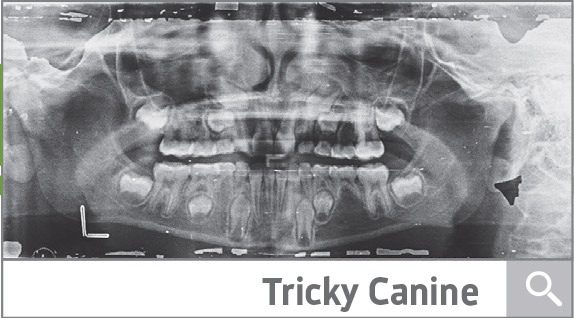

Tricky Canine Substitution Case

A 10-year-old patient with a handful of complicating details, including minimal roots, missing U5s, U2s, LL4, LR5 and more. The doc has questions on substitutions and extractions. Help him out.